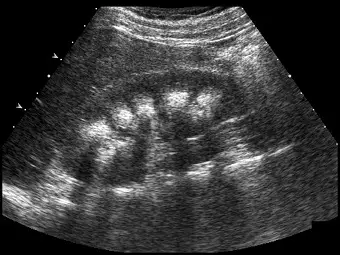

腎臟超音波掃描時,發現多處的腎錐體( pyramids )呈現高回音性,下圖最有可能的診斷為何?

本題主要考查腎臟超音波(renal ultrasound)中,皮質與髓質(cortex and medulla)回音性(echogenicity)變化的臨床意義。正常情況下,腎臟的超音波解剖結構由外至內分別為:相對於肝臟或脾臟呈現等回音或稍低回音的「腎皮質」、含有較多水分(尿液)而呈現低回音(hypoechoic)的「腎髓質(包含腎錐體)」,以及含有大量脂肪、血管與集尿系統而呈現高回音(hyperechoic)的「腎竇(renal sinus)」。當腎錐體出現異常的高回音時,代表該區域發生了病理性的物質沉積,最典型的狀況即為鈣質沉積。

觀察題目所附之腎臟灰階超音波影像,可以發現以下特徵:

- 腎皮質(Renal cortex):呈現相對正常的偏低回音性。

- 腎髓質 / 腎錐體(Renal medulla / pyramids):影像中可見多個位於皮質下方的錐狀至圓形結構,呈現極為明顯的高回音(hyperechoic,亮白區域)。這使得原本應該是「皮質較亮、髓質較暗」的正常皮質髓質分界(corticomedullary differentiation)發生了反轉(reversal)。

- 腎竇(Renal sinus):中央區域依然為正常的高回音。 此種多發性、廣泛分佈於腎錐體的高回音影像,是典